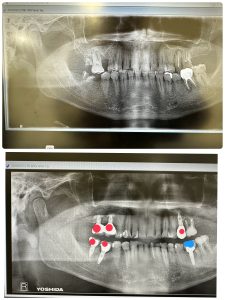

右側は約14年経過、安定している💪

赤印はスプラインツイスト

青印は、エニーリッジ